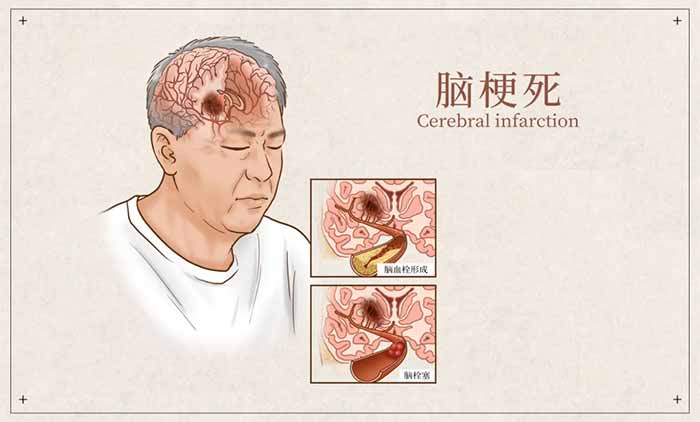

急性后循环缺血性卒中,是由于后循环血管狭窄、闭塞导致血流灌注不足或血栓栓塞,进而引发脑组织缺血性损伤。这类卒中约占所有缺血性卒中的20%–25%,是导致患者残疾和死亡的重要原因之一。

其中最严重的类型之一是脑干梗死。近年来流行病学调查显示,脑梗死不仅呈现“年轻化”趋势,发生在后循环区域的梗死比例也在升高。

▲ 后循环梗死的症状往往不典型

▲ 后循环缺血十分危险

▲ 脑干梗死